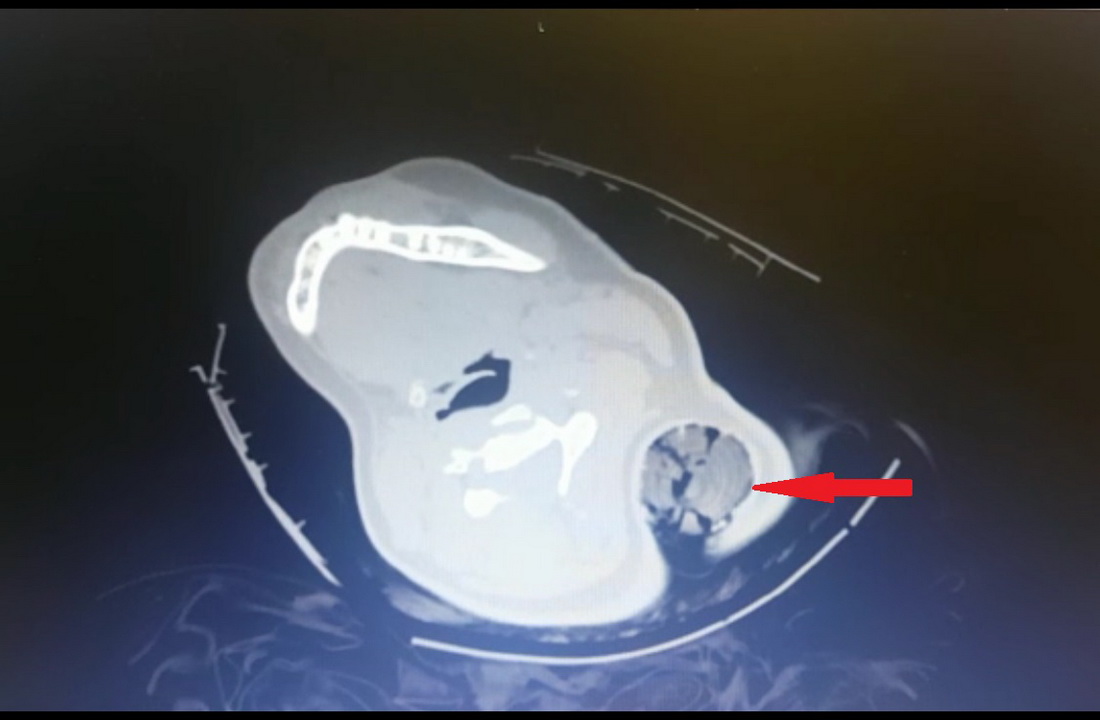

31 Temmuz 2019 da başka bir aracın sıkıştırması sonucu kaza geçiren aracın yolcu koltuğunda oturan 19 yaşındaki B.Ö.’nün boynuna saplanan 30 santimetrelik tahta kazık sol koltuk altından çıktı. Tahta kazığı ameliyatla çıkaran KSÜ Tıp Fakültesi Ortopedi ve Travmatoloji Anabilim Dalı Öğretim Üyesi Dr. Bülent Güneri, genç kızın sadece bir kaburgasının kırıldığını, sinir ve damarlarının zarar görmediğini belirterek, "Tıp literatüründe bu şekilde boyundan girip koltuk altından çıkan bir cisim yok" dedi.

Kazada ağır yaralanan genç kız, vücuduna saplanan tahta kazık ile KSÜ Tıp’a götürüldü. Hastaneye bilinci açık olarak gelen B.Ö.’ye acilde yapılan ilk değerlendirmenin ardından acil hekimlerince Ortopedi ve Travmatoloji Anabilim Dalı Öğretim Üyesi Dr. Bülent Güneri’ye haber verdi. Hastanın yanına gelen Güneri, çekilen tomografi görüntülerini inceledikten sonra genç kızı ameliyata aldı. Yaklaşık yarım saat süren ameliyatla tahta kazık çıkarılırken, kazığın sinir ve damarlara zarar vermemesi nedeniyle mucize eseri hayatta kalan genç kız olayı bir kaburga kırığı ile atlattı. B.Ö. hastanede gördüğü bir haftalık tedavi sonrası sağlığına kavuşarak taburcu edildi.

Bu tür vakalarda genellikle sinir ve damar yaralanmalarının olduğunu ancak bu olayda sinir ve damar yaralanmasının olmayışının çok ilginç olduğunu ifade eden Güneri, “Hastayı acil ameliyata aldık. Ameliyat esnasında Göğüs Cerrahisi hocamız Dr. Öğretim Üyesi Ahmet Acıpayam ve Kalp ve Damar Cerrahisi hocamız Doç. Dr. Mehmet Acıpayam hazır bulundular herhangi bir komplikasyona yönelik olarak. Ameliyathanede yaptığımız değerlendirmeden sonra anestezi altında yaklaşık 30 santimetrelik tahta bir kazık çıkardık hastadan. Kazık, hastanın saçlarını dolayarak boynundan girip sol kol altından çıkmıştı. Ve böyle kirli bir yaralanma, ev dışında, sokakta olan bir yaralanma enfeksiyon açısından oldukça risklidir. Ama ameliyat esnasında yaptığımız girişimler ve titizlikle uyguladığımız antibiyotik tedavisi sayesinde hastamızda bir enfeksiyon meydana gelmedi” diye konuştu.

Olayın çok ilginç olması nedeniyle daha önce bu ve buna benzer bir vakanın olup olmadığını araştırdığını belirten Dr. Bülent Güneri, şöyle devam etti: “Tıp literatüründe benzer yaralanmalar var, metal ve tahta cisim saplanmaları görülüyor. Ancak bu şekilde boyundan girip koltuk altından çıkan bir cisim yaptığım taramalarda tespit etmedim. Ancak literatürde bildirilen vakalarda çok ciddi sinir yaralanmaları ya da omuriliğe saplanıp da enfeksiyona yol açan bu nedenle tedavi görmek zorunda olan hastalar mevcut. Bizim hastamızda herhangi sinir veya damarsal yapıya denk gelmedi ancak bir kaburga kırığına yol açtı ve içeride bol miktarda hastanın saç bulunduğu için bizi daha çok uğraştıran içeride bulunan saç parçalarıydı. Biz, kazığın gidiş yönü boyunca açmayıp, kazığı ters yönde çıkartıp içeriye bol miktarda steril sıvıyla yıkama uyguladık ve iyi bir antibiyotik tedavisi verdiğimizi düşünüyorum. Bu sayede de bir sorun meydana gelmedi. Hasta oldukça talihli bene, birçok kişi bunu mucize olarak değerlendirebilir. Beni ve ekibimi oldukça şaşırttı. Ve hastayı birlikte değerlendiren cerrahi branştan diğer hocalarımızı da oldukça şaşırttı. Adeta mucize gibiydi diyebilirim.”